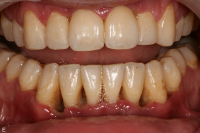

Parodontal stabilitet karakteriseras av framgångsrik behandling genom kontroll av lokala och systemiska riskfaktorer, vilket resulterat i

- minimal blödning vid sondering (BVS < 10 % av tandytorna)

- fickdjup < 3 mm

- ingen progressiv parodontal nedbrytning/vävnadsförlust

- optimal förbättring i övriga kliniska parametrar hos behandlad parodontitpatient.